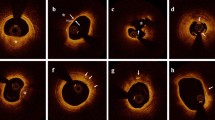

Quantitative coronary angiography (QCA) was performed using the Cardiovascular Angiography Analysis System (CAAS, 5.10, Pie Medical Imaging B.V., Maastricht, the Netherlands). Culprit vessels and lesion sites were identified, and the length of the culprit lesions, reference vessel diameter, minimal lesion diameter, and degree of diameter stenosis were measured. OCT data were recorded using the C7-XR OCT intravascular imaging system (OCT C7 Dragonfly, St. Jude Medical, St. Paul, MN, USA). Quantitative and qualitative analyses of underlying plaques were performed by two independent operators as described in a previous study [10]. Any discordance was resolved by consensus with a third reviewer. Using established diagnostic criteria [12], the plaque and thrombus type were identified based on established OCT diagnostic criteria, along with identification of microchannels, cholesterol crystals, macrophages, and thin-cap fibroatheroma (TCFA). The lesion length, minimal lumen area, minimal thickness of the fibrotic cap, length of the residual thrombus, length of the lipid core, maximal arc of the lipid core, and average arc of the lipid core were measured as described previously [13] (Fig. 1)

Typical optical coherence tomography (OCT) images of plaque characteristics. a A typical image of a patient with STEMI and plaque erosion characterized as intact and rouHbA1c intima attached with small white thrombus. b A typical image of a patient with STEMI and plaque rupture characterized as ruptured intima (arrow) backed with a big cavity. c–h Representative OCT images, including TCFA, micro-channel, macrophage accumulation, spotty calcification, cholesterol crystal, and lipid core measured with the lipid arc, are presented in turn (arrows). The asterisk marks the position of the OCT guide wire